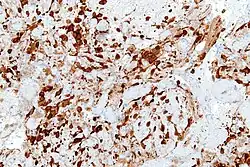

Utility

Detection of NSE with antibodies can be used to identify neuronal cells and cells with neuroendocrine differentiation. NSE is produced by small-cell carcinomas, which are neuroendocrine in origin. NSE is therefore a useful tumor marker for distinguishing small-cell carcinomas from other tumors.[7]